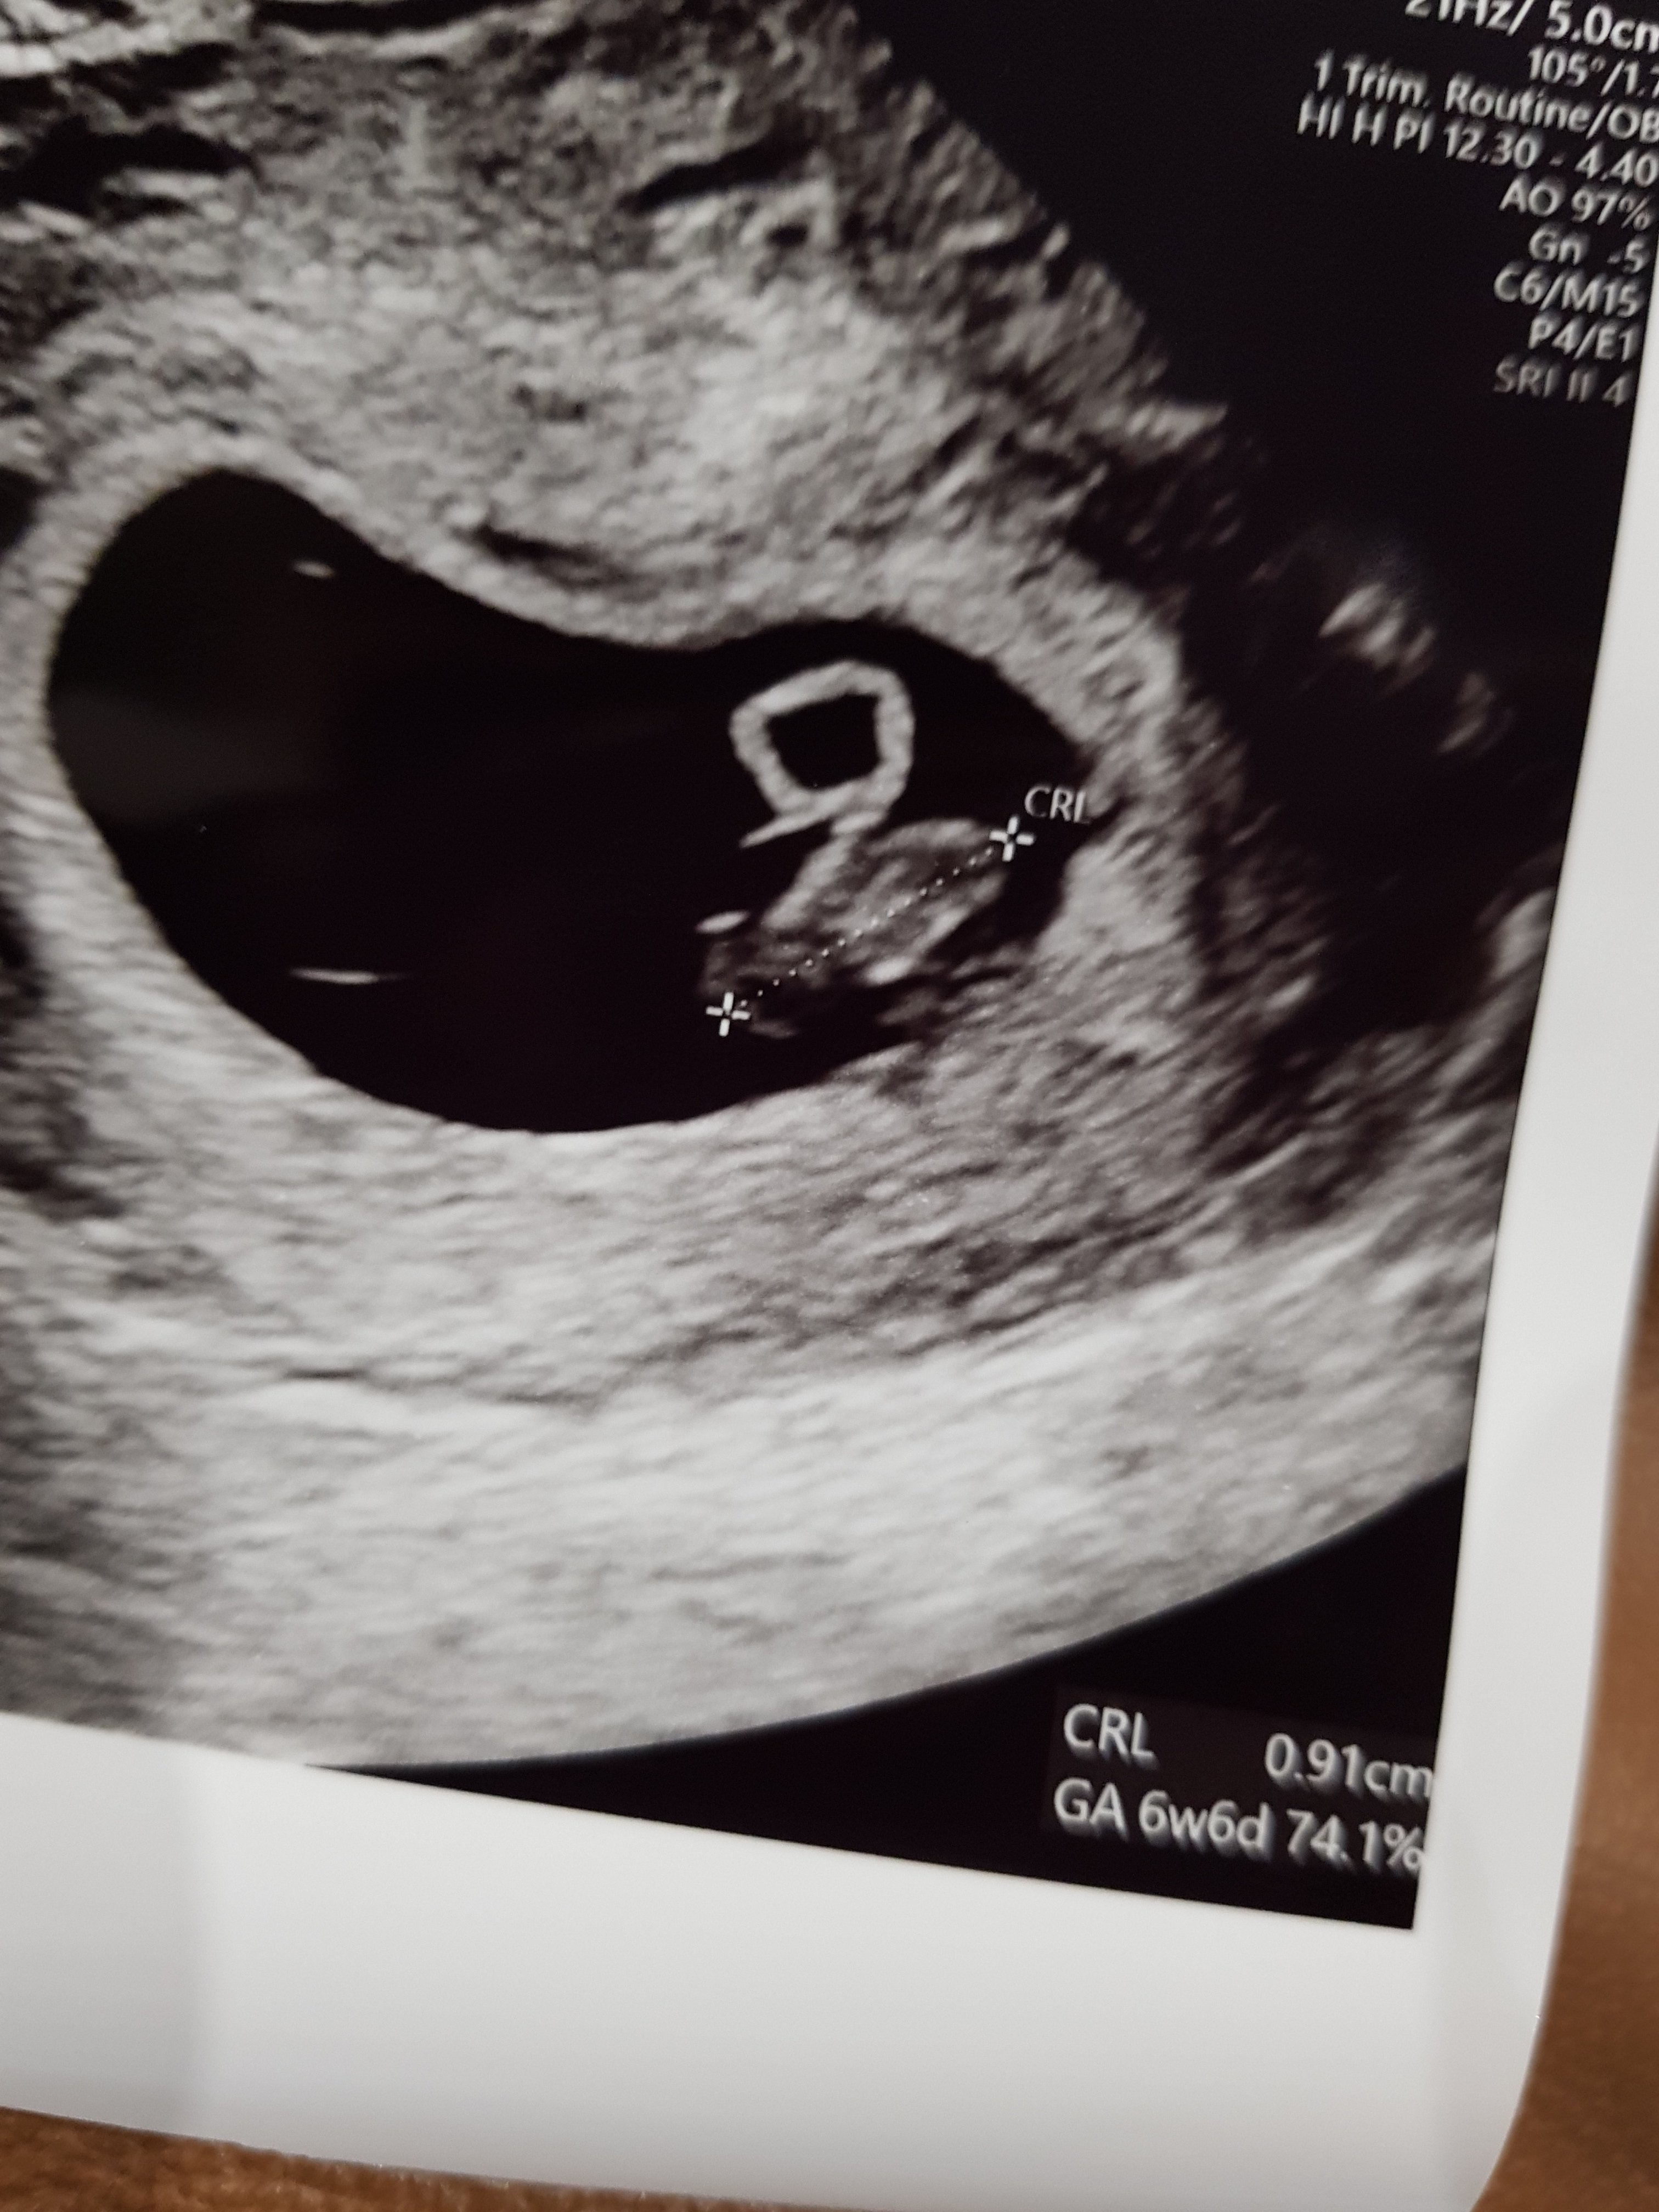

Ojej... zostawilam tak Was w niewiedzy. Ale za bardzo sie podjaralam. Zobaczylam swojego dzidziusia i serduszko (nie sluchalam, bo mam przyjaciela lekarza i doppler na takim etapie moze przegrzac tkanki) ❤ no kocham max tego dzidziocha - cale 9mm czlowieka

nigdy nie szukalam lekarza, ktory pracowalby w szpitalu, a tu sam we wlasnej osobie ordynator sie znalazl. Poznalismy sie rok temu przy łyżeczkowaniu, ale mam nadzieje, ze tym razem skonczy sie lepiej ❤ termin z wielkosci zarodka rozni sie jednym dniem od terminu om, czyli jutro bedzie 7+0

Zobacz załącznik 1193377